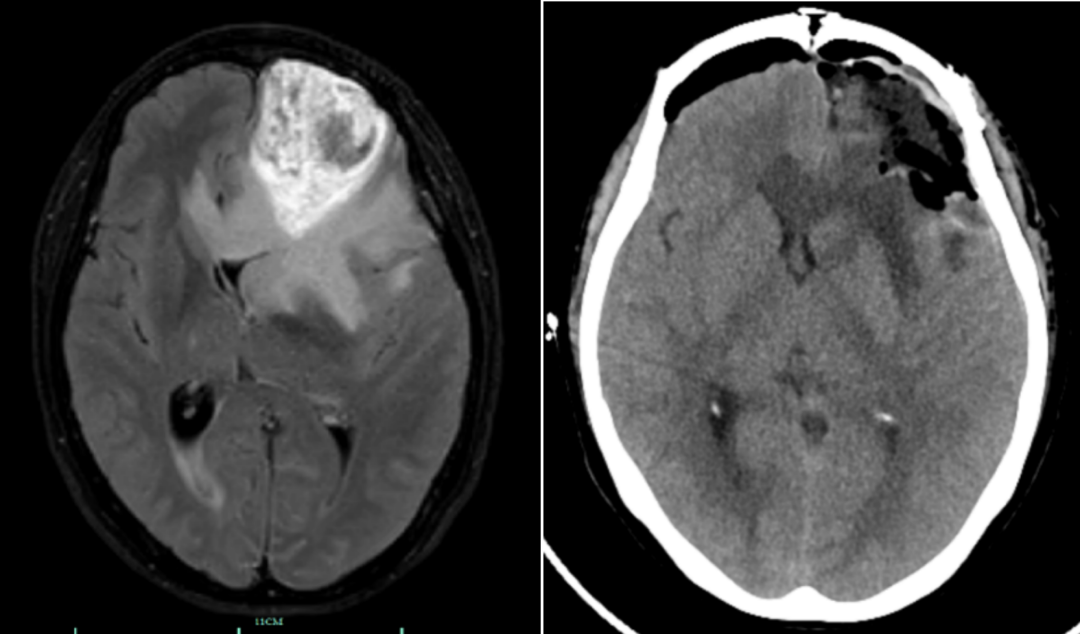

14日,王女士在家人的陪伴下来到宁大附属人民医院(鄞州人民医院)就诊,检查结果显示,王女士患有恶性脑胶质瘤,且因为肿瘤巨大导致严重的脑水肿引起严重的颅内压增高,才会出现频繁的呕吐症状。

“像这种情况就像体内埋着一颗定时炸弹,若不立即进行手术切除肿瘤,随时会有生命危险。”8月15日,神经外科主任高峰带领团队为王女士施行了神经导航下“左额开颅脑肿瘤切除术”。历时5小时,将肿瘤精准地完整切除。